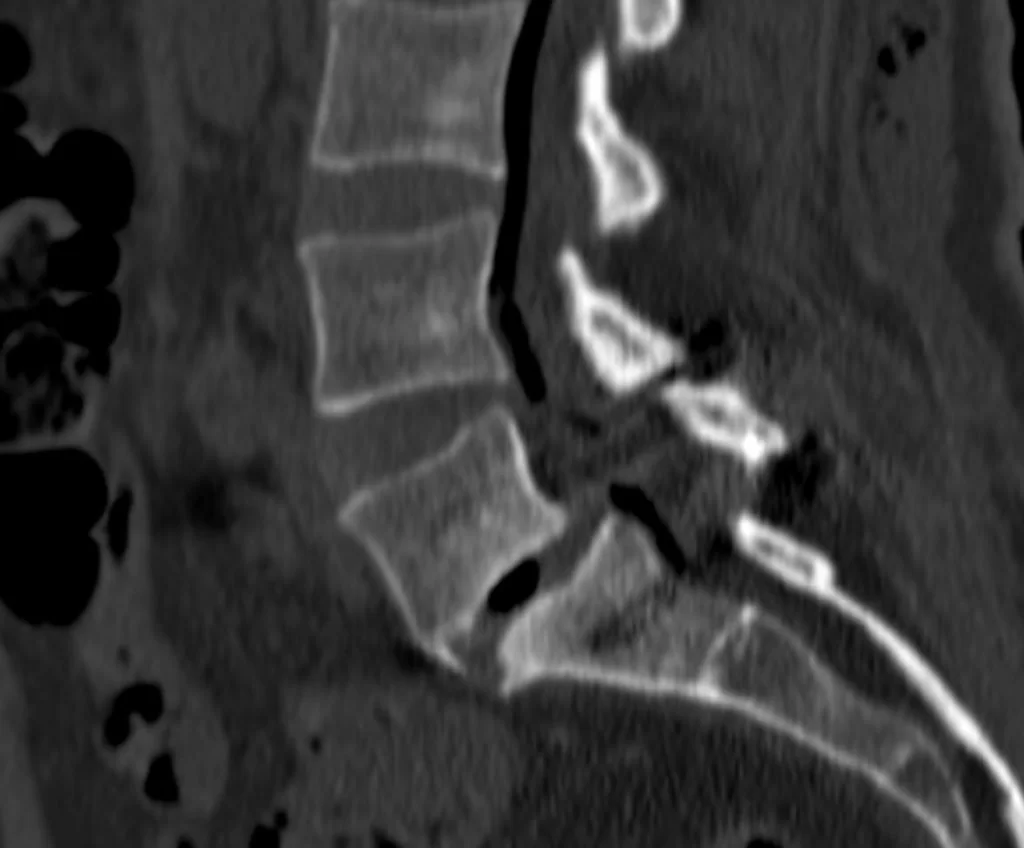

Ο απεικονιστικός έλεγχος ανέδειξε σπονδυλολίσθηση 2ου βαθμού σε έδαφος σπονδυλόλυσης στο ύψος Ο5-Ι1.

Διενεργήθη διαδερμική (ελάχιστα επεμβατική) σπονδυλοδεσία στο επίπεδο Ο5-Ι1